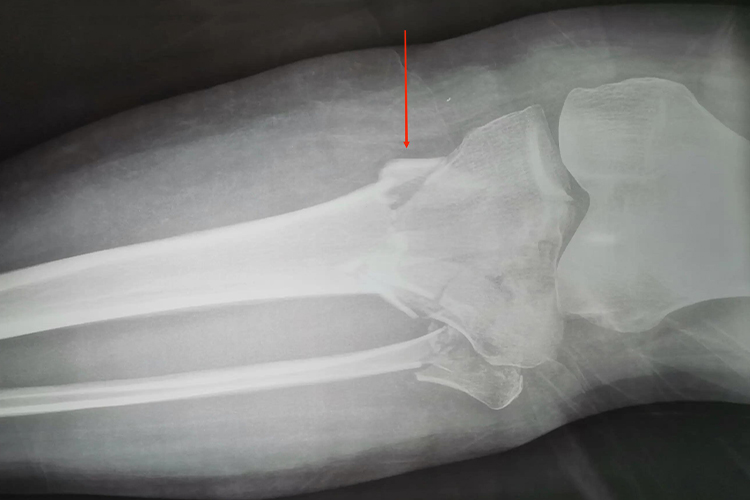

左侧胫骨平台骨折的患者进行X线、CT等影像学检查时,可见胫骨外侧平台出现劈裂、分离样的骨折表现,严重时可有压缩性骨折,可伴有半月板撕裂、膝关节脱位等并发症。

患者发生左侧胫骨平台骨折后,受伤的膝部会有明显的肿胀、疼痛,影像学检查可见胫骨平台出现不同程度的劈裂、关节面塌陷等表现。